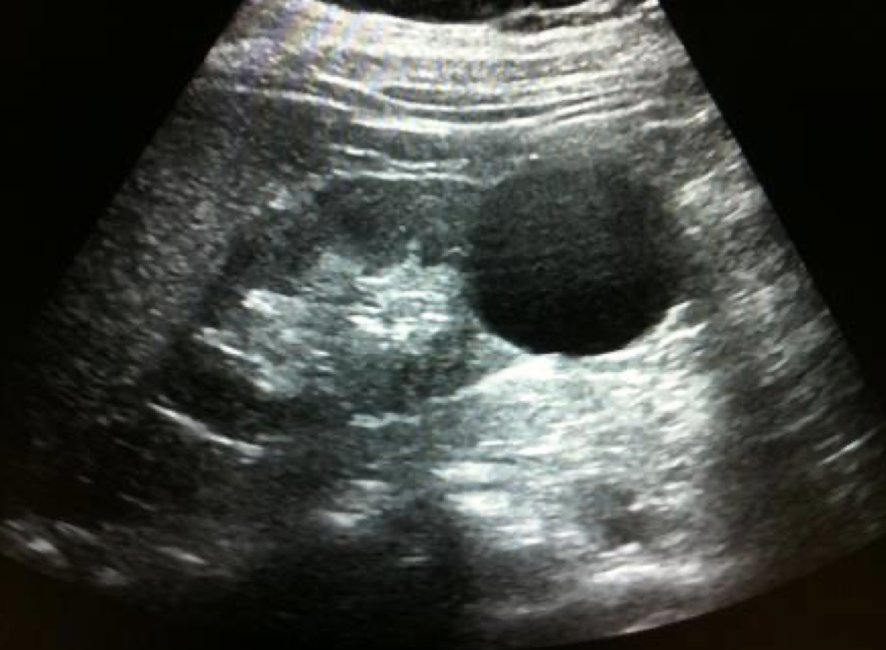

complex mass

shows characteristics of both cystic and solid lesions

may contain septations, thick walls > 1 mm, nodularity, calcifications, internal echoes from areas of necrosis, hemorrhage, or abscess/infection

** if there is septation in cyst, put color box on it, especially if its thick

complex cyst

may contain septations, thick walls, calcifications, internal echoes, and mural nodularity

considered malignant until proven benign, especially if septa >1 mm thick with vascular flow on color or Power Doppler

any irregularity at the base of the cyst should be considered a malignant growth

??

has septations and solid components